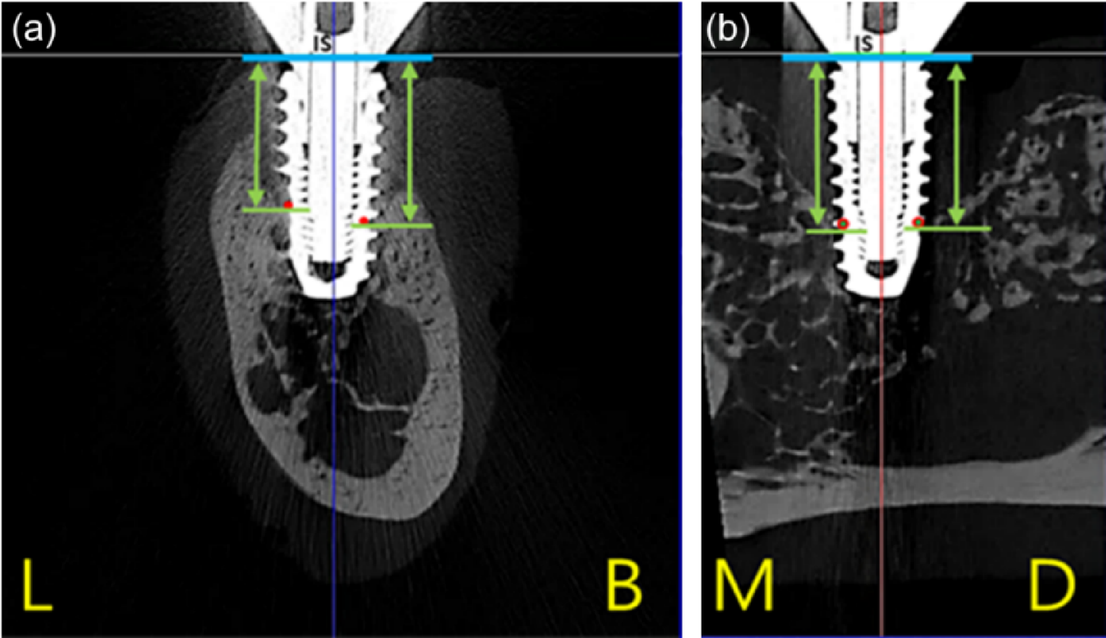

Fig. 5

Peri-implant bone loss was evaluated by measuring linear dimensions in four directions from the implant shoulder to the most coronal point of surrounding bone attached implant threads on micro-CT cross sections: Buccolingual section (a) and mesiodistal section (b). (L: lingual, B: buccal, M: mesial, D: distal)